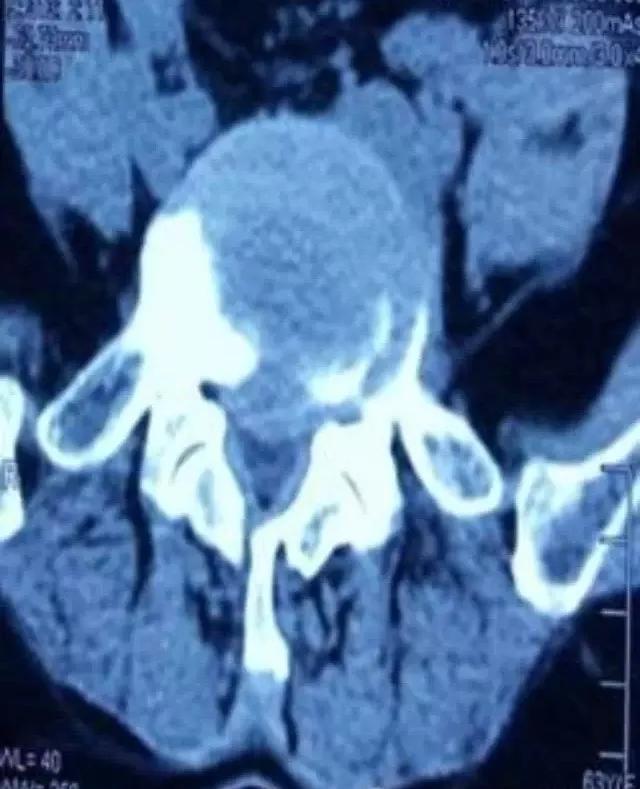

CT:诊断符合率96% —100%,正常CT椎管形态为三角形或球形,狭窄的可显示为三叶草、牛角、猫耳形。Korkard测量侧窝神经根管矢径大于5mm 为正常,4 mm 为临界.小于 3mm 为狭窄。椎管与椎体矢状径比值在椎弓板上切迹层面小于0.45 ,在椎间盘层面小于0.35可以确诊,硬膜囊与椎管矢状径比值如低于0.6 以下可以确认。近年来又有CT计算机图形计算椎管横截面积CSAC自L1-S1,逐渐加大,硬膜囊横截面积(CSADS)自L1-S1,逐渐减小,来评估椎管狭窄。 MRI :它不能提供精确的定位与清晰的图像,诊断符合率占 82%一 91%,但在鉴别诊断方面可显示椎管。